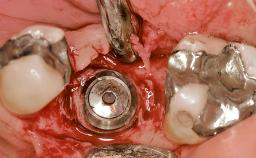

Early Placement of an Implant in a Maxillary Right Central Incisor Site

This 41-year-old female patient was referred to the clinic for the replacement of the right central incisor, since the tooth had developed a root fracture in the long axis that made extraction necessary. The healthy, non-smoking patient was first seen with the tooth still in place. A detailed Esthetic Risk Assessment was performed.The patient was worried about her dental esthetics and had high expectations for a successful treatment outcome from an esthetic point of view. The patient had a medium lip line that displayed parts of the gingiva in the anterior maxilla upon smile.

Bone Augmentation Horizontal|Simultaneous

Augmentation Materials Autogenous chips|Xenogenous|Membrane